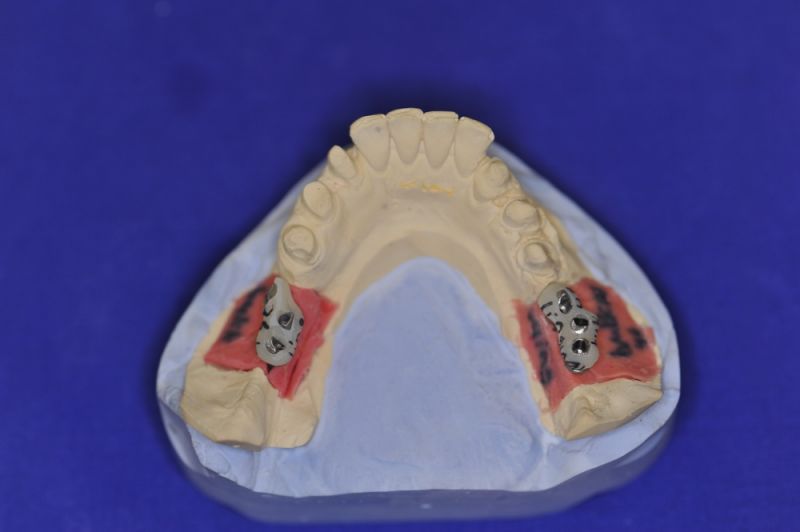

Es war eine Kombination aus Schmerzen bis an die Suizidgrenze, beschränkten wirtschaftlichen Möglichkeiten, sehr stark eingeschränkten Möglichkeiten der für Implantate zur Verfügung stehenden Knochenverhältnisse in einem stark atrophierten Unterkieferseitenzahnbereich und zudem dann auch noch durch auftretenden Problemen bei der Implantatinsertion und nachfolgenden Versorgung der Implantate.

Die Problematik der Implantatversorgungen kann man in einer Analogie folgendermaßen darstellen. Die räumlich beengten Zustände gleichen dem Tanz eines Paares auf einer Briefmarke, und der gleichzeitigen Schritt- und Fusshaltung, dass beim Tanzen die Schuhe geputzt werden können!